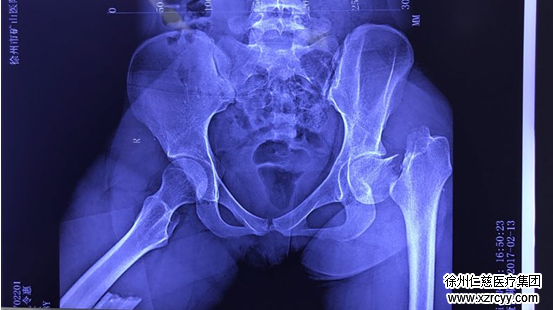

悲劇的開(kāi)場(chǎng)要從今年2月中旬說(shuō)起。2月13日早上,惠惠像往常一樣從家里出門(mén)去上學(xué),下樓時(shí)不慎一腳踩空,從幾節(jié)高的樓梯上跌落,造成“雙下肢嚴(yán)重骨折”。家人當(dāng)即將其送至附近醫(yī)院救治。

于是,在家人的陪同下,惠惠去醫(yī)院進(jìn)行了復(fù)查。很快,CT報(bào)告出爐??吹狡永镲@示的影像,惠惠和家人頓時(shí)傻了眼:植入惠惠腿里的鋼釘竟然打偏了,也正是這根錯(cuò)位的鋼釘,讓她每天都在承受著鉆心的疼痛!更為嚴(yán)重的是,由于耽擱時(shí)間較長(zhǎng),惠惠的左股骨頸也已隨之移位,左下肢已經(jīng)發(fā)生了短縮畸形,如果不及時(shí)糾正的話,將造成繼發(fā)性損傷,導(dǎo)致股骨頭壞死。到那個(gè)時(shí)候,這個(gè)年輕女孩則必須要面臨股關(guān)節(jié)置換。然而目前市面上最好的人工股關(guān)節(jié)的使用期限也僅僅只有40年,并且價(jià)格比較昂貴,這就意味著,如果二次復(fù)位手術(shù)失敗的話,惠惠將至少面臨兩次股關(guān)節(jié)置換,這對(duì)其本人和家人來(lái)說(shuō),無(wú)論是在經(jīng)濟(jì)上還是身體和精神上都要承擔(dān)難以想象的代價(jià)。